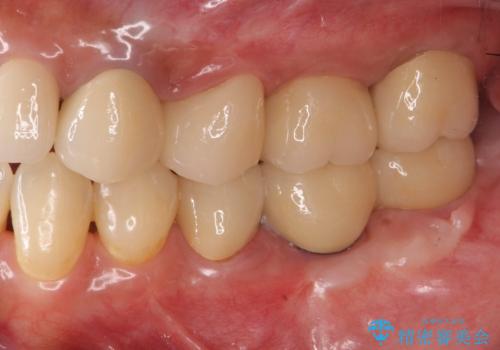

遊離歯肉移植術を併用した、破折歯のインプラント治療

抜歯後、インプラントを用いて咬合機能を回復すると共に周囲に強固な角化歯肉を移植することによりより長期にわたり安定したインプラント周囲環境となるよう治療を計画します。

インプラント周囲の角化歯肉が存在することにより、歯ブラシがしやすくなりインプラントにトラブルが起きる確率を減らしより長期的な予後を望むことができます。